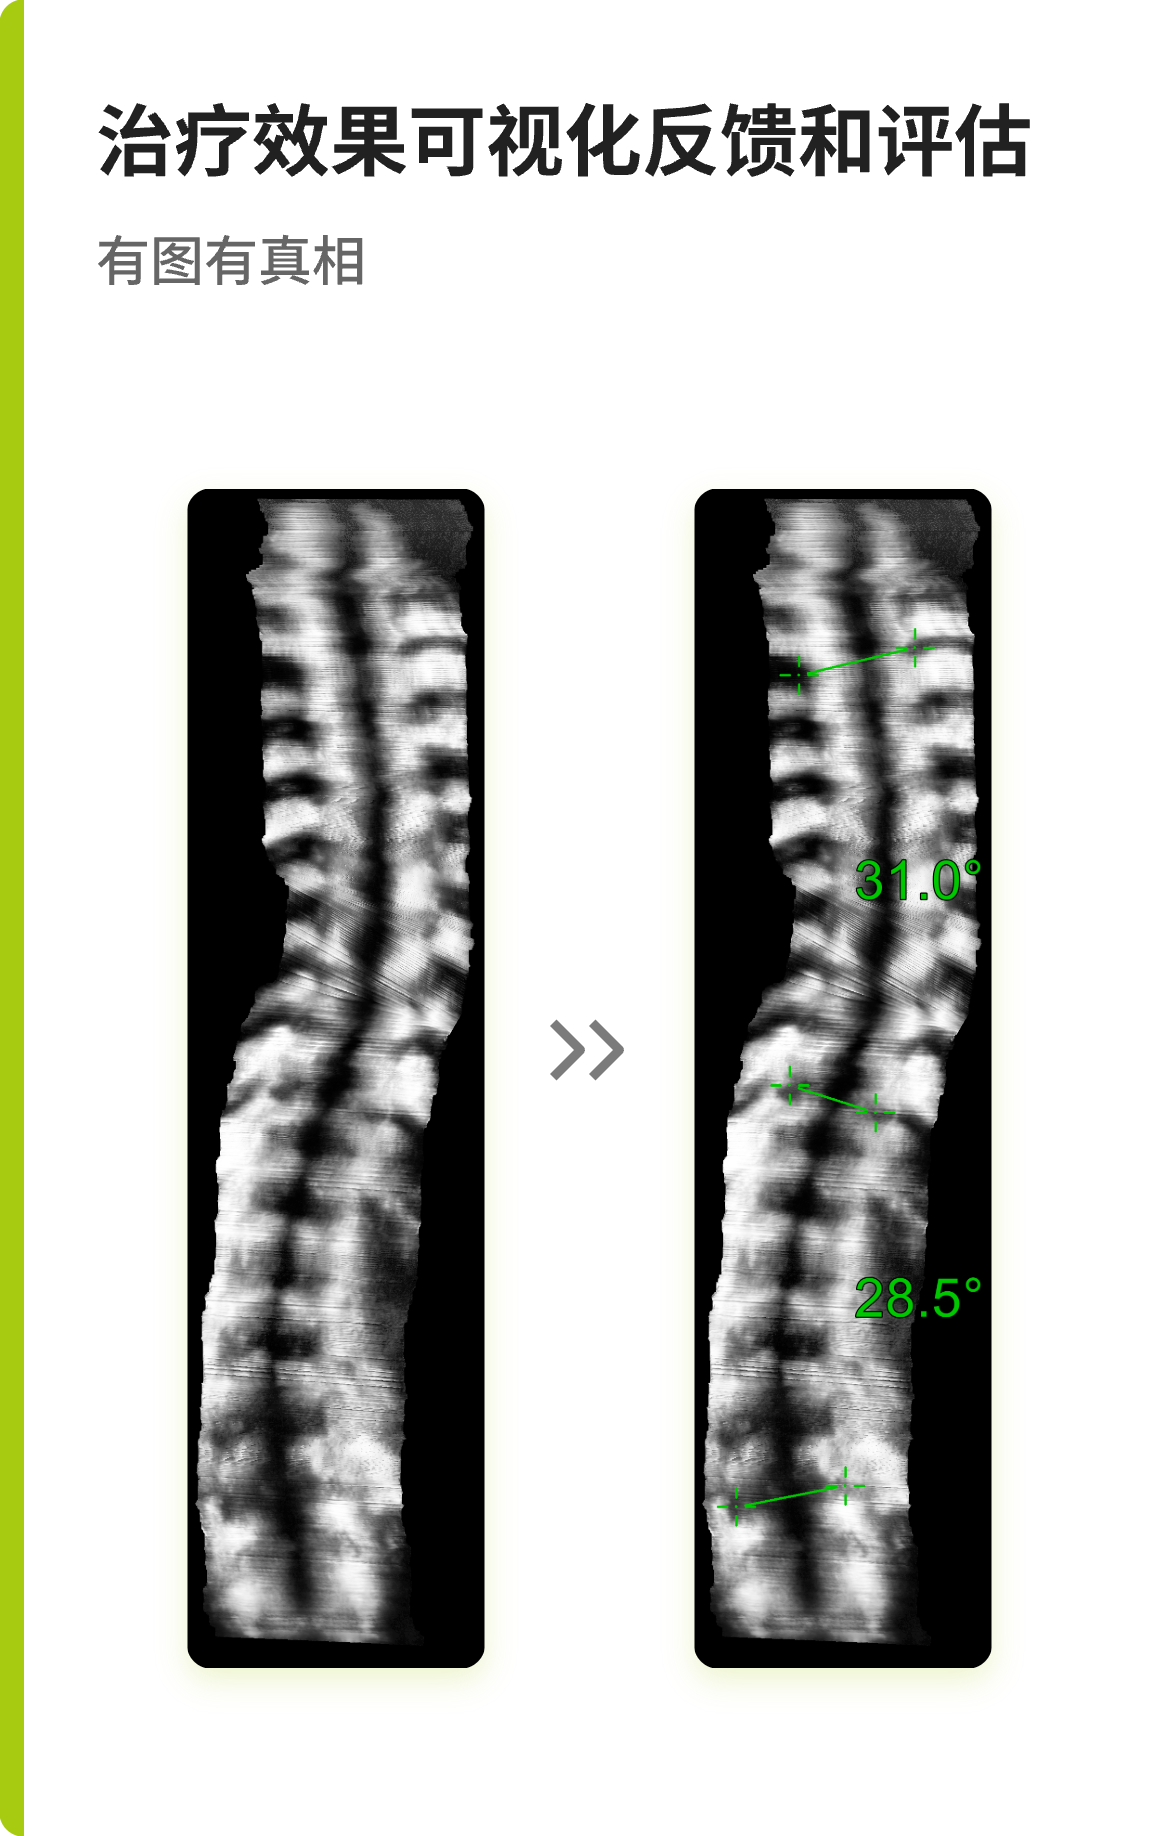

“ 获取脊柱T1-L5全长冠状位超声图像•定量评估脊柱侧弯程度 ”

Scolioscan Air AI 辅助测量算法可以自动识别脊柱特征点并测量每一节椎体角度,帮助医生快速计算脊柱弯曲角度,大幅缩短报告生成时间,提升检查效率。